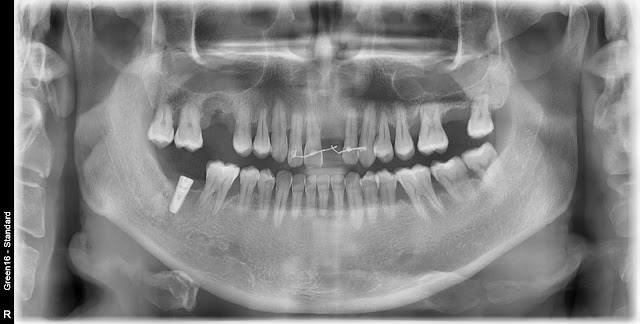

The patient is a 44-year-old male.He is considering implant placement in area 16, but there is significant damage to the alveolar bone.In this case, socket preservation was performed simultaneously with the extraction.The pre-extraction condition.I have confirmed the pre-extraction condition. Symptoms of periapical infection are evident, and the maxillary sinus membrane appears to be thickened.

The pre-operative condition is shown here. The thickening of the maxillary sinus membrane appears to have disappeared. Based on this level of healing, it seems that a crestal approach implant placement may be feasible.

The post-operative condition after crestal approach implant placement and bone grafting.

This is a radiograph taken during scanning